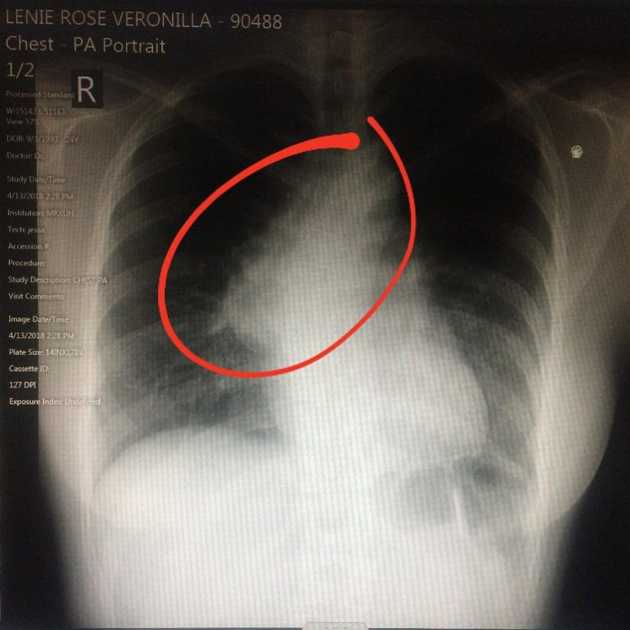

The result of the chest x-ray was a suspected mass. I was recommended for a chest CT scan.

Chest X-Ray

The chest CT scan result confirmed an anterior mediastinal mass measuring 4.6 x 7.2 x 7.9 cm. Primary consideration was thymoma. Its mainstay treatment is surgery.